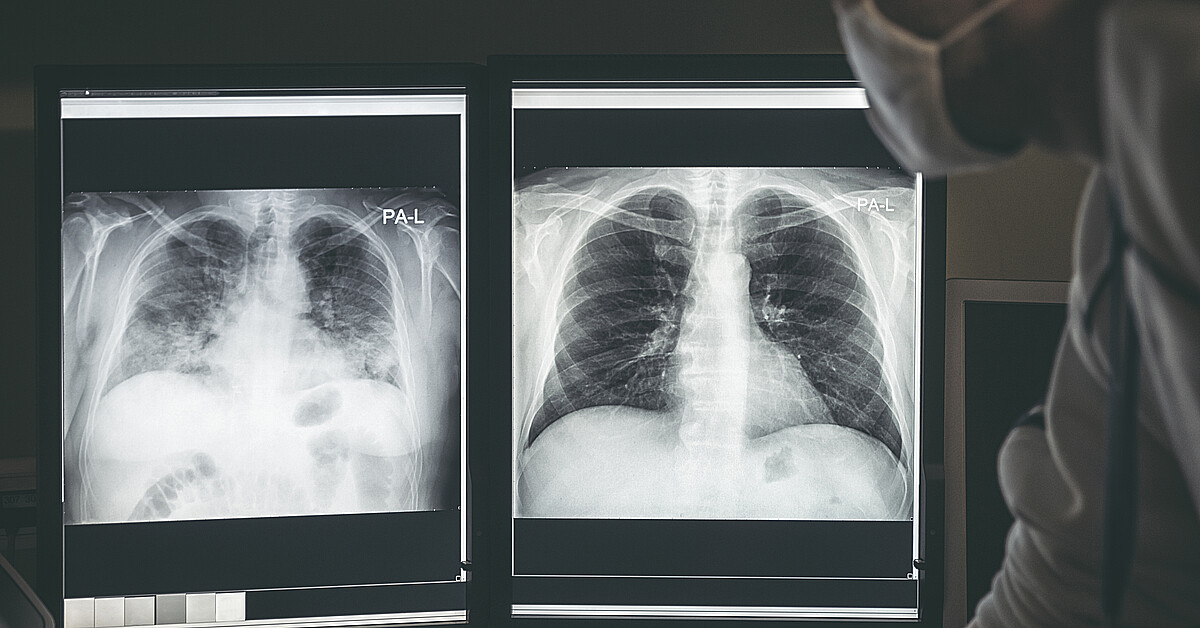

Lo llevaron al hospital donde le tomaron una radiografía que reveló que tenía la dentadura postiza de 1,5 pulgadas atascada en las vías respiratorias de su pulmón, según el estudio de caso publicado esta semana en la revista médica Cureus.